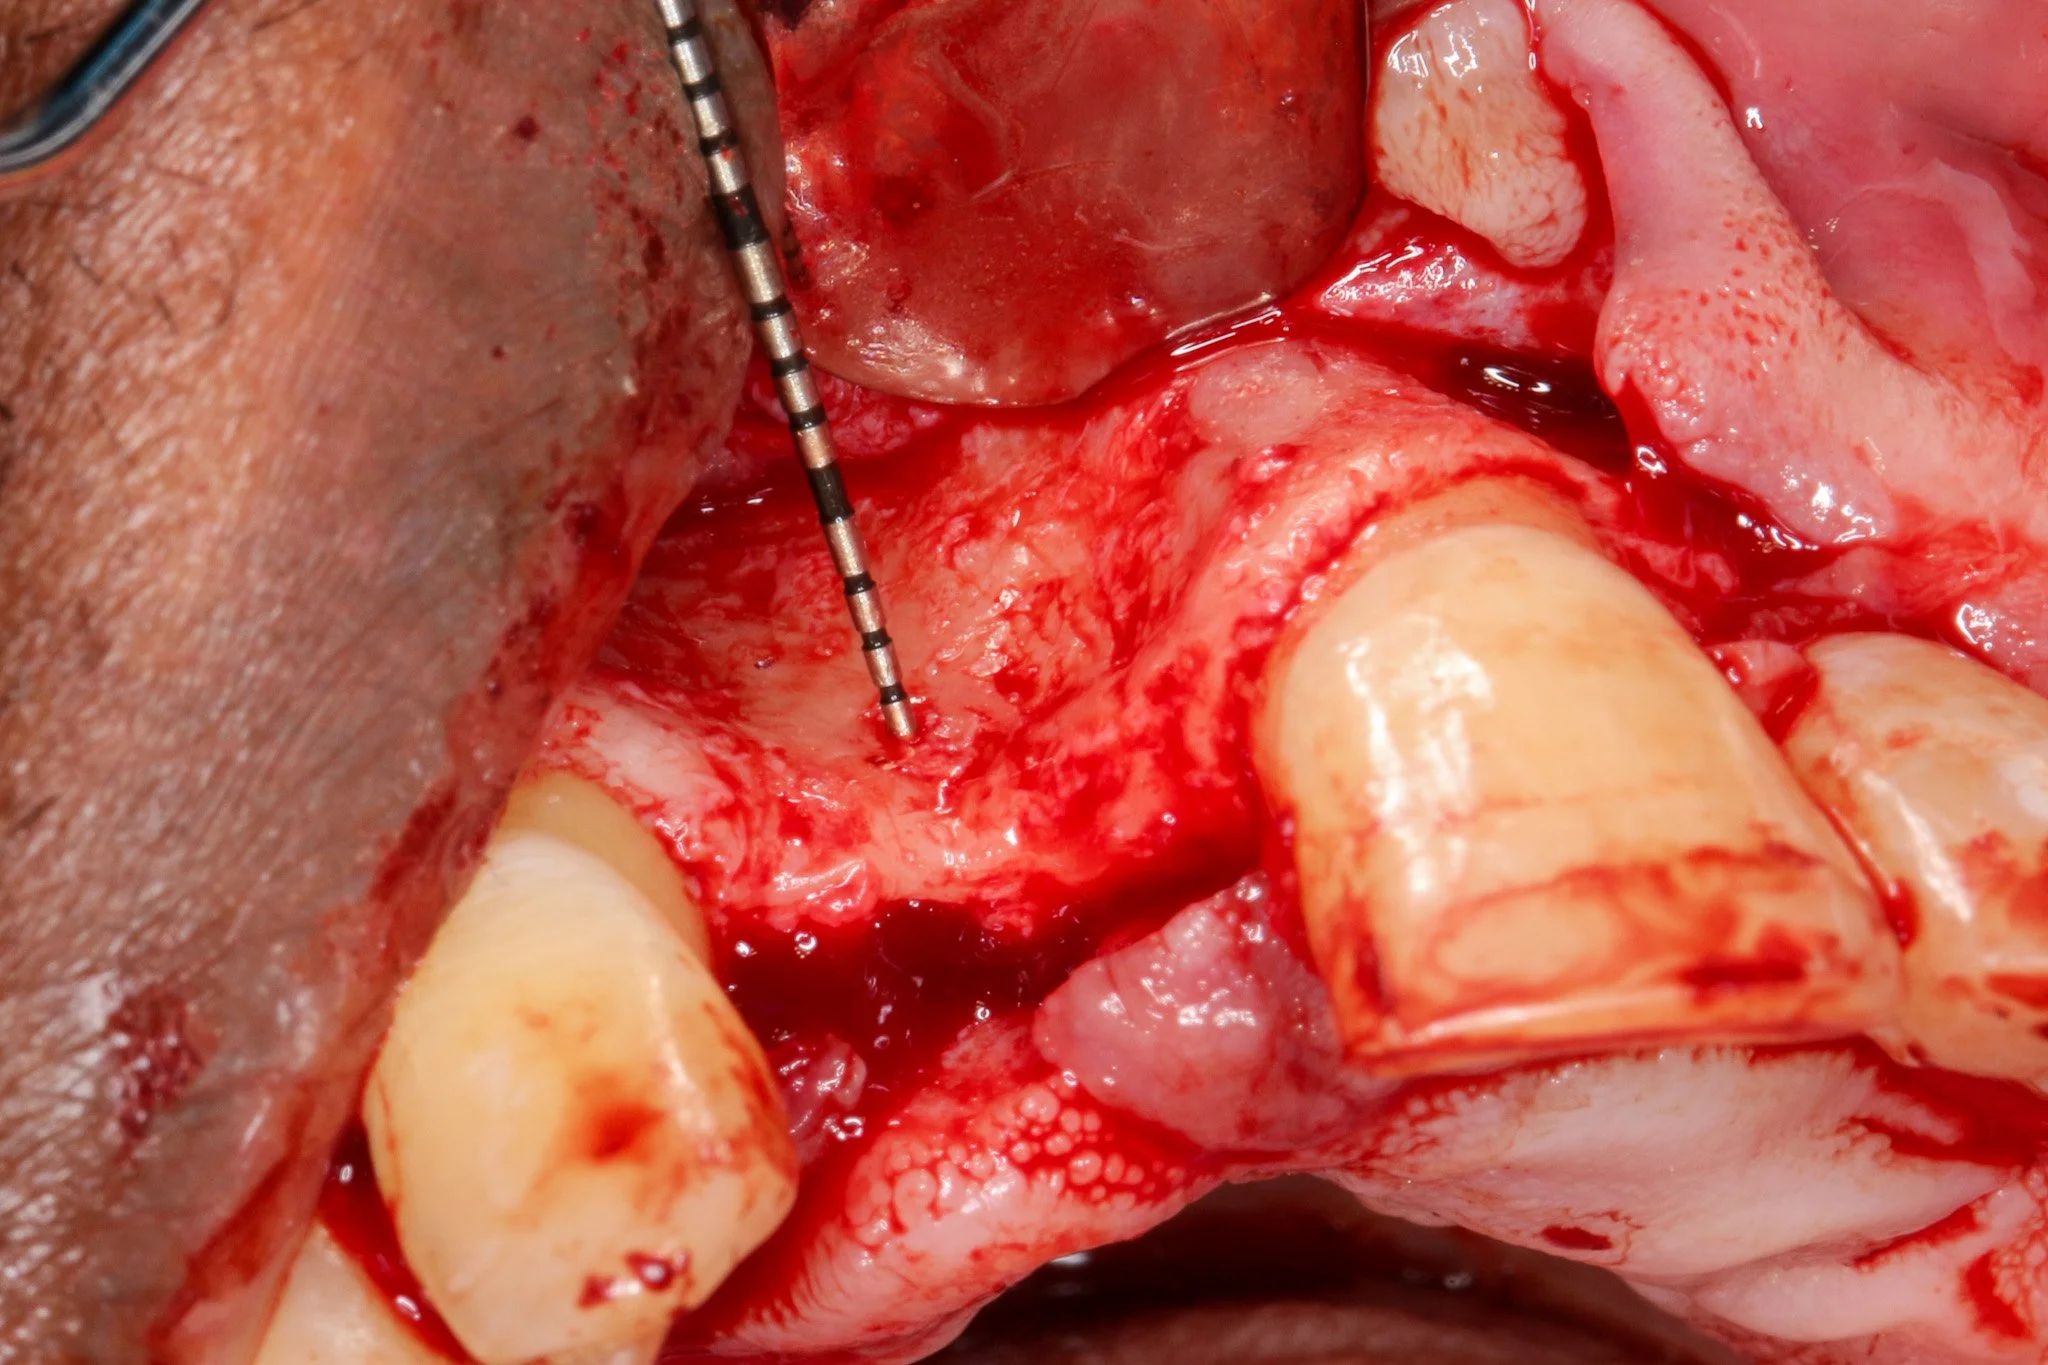

Periosteal releasing incision was executed to achieve tennsion-free, passive primary closure. Wang and colleagues 2001 demonstrated that passive flap closure significantly reduces membrane exposure rates and enhances bone regeneration outcomes. It is important to preserve blood supply to soft tissue while allowing adequat flap advancement when periosteal releasing incision is made.

A double-layer resorbable membrane technique was employed with tacking srew fixation to ensure graft stability and space maintenance. The use of resorbable membranes has been extensively validated in the literature, with systematic reviews by Rocchietta et al. (2008) confirming comparable outcomes to non-resorbable membranes while eliminating the need for 2nd stage surgery. Urban et al. (2009), the dual-membrane approach provides enhanced barrier function and structural support.